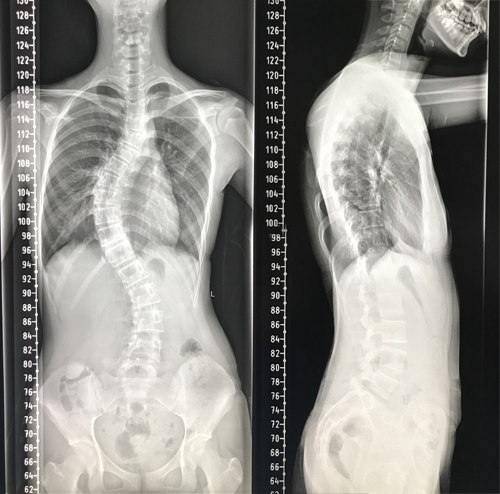

患者小冰今年13岁,4个月前家属发现小冰肩背部明显不对称,严重影响美观,且无法平卧入睡,经多方咨询,慕名来临床医学院/附属医院骨三科就诊。专科检查发现患者脊柱呈明显S型弯曲,躯干向右侧倾斜,双肩不等高,剃刀背畸形,主胸弯Cobb角度达60°,脊柱畸形较为严重。该院骨三科朱述浪主任带领脊柱外科团队,详细讨论了小冰的病情。

术后护理团队制定了详细的护理计划,严密观察患者生命体征及切口情况。在科室全体医护人员的共同努力下,小冰术后各项指标恢复良好,术后68小时便拔除引流管,并佩戴支具下床活动。复查脊柱全长片提示脊柱S型弯曲得到了充分矫正,双肩等高,剃刀背畸形消失。术后,小冰终于可以正常平卧睡觉,而且身高达到164.5cm,较术前足足增高了4.5cm。